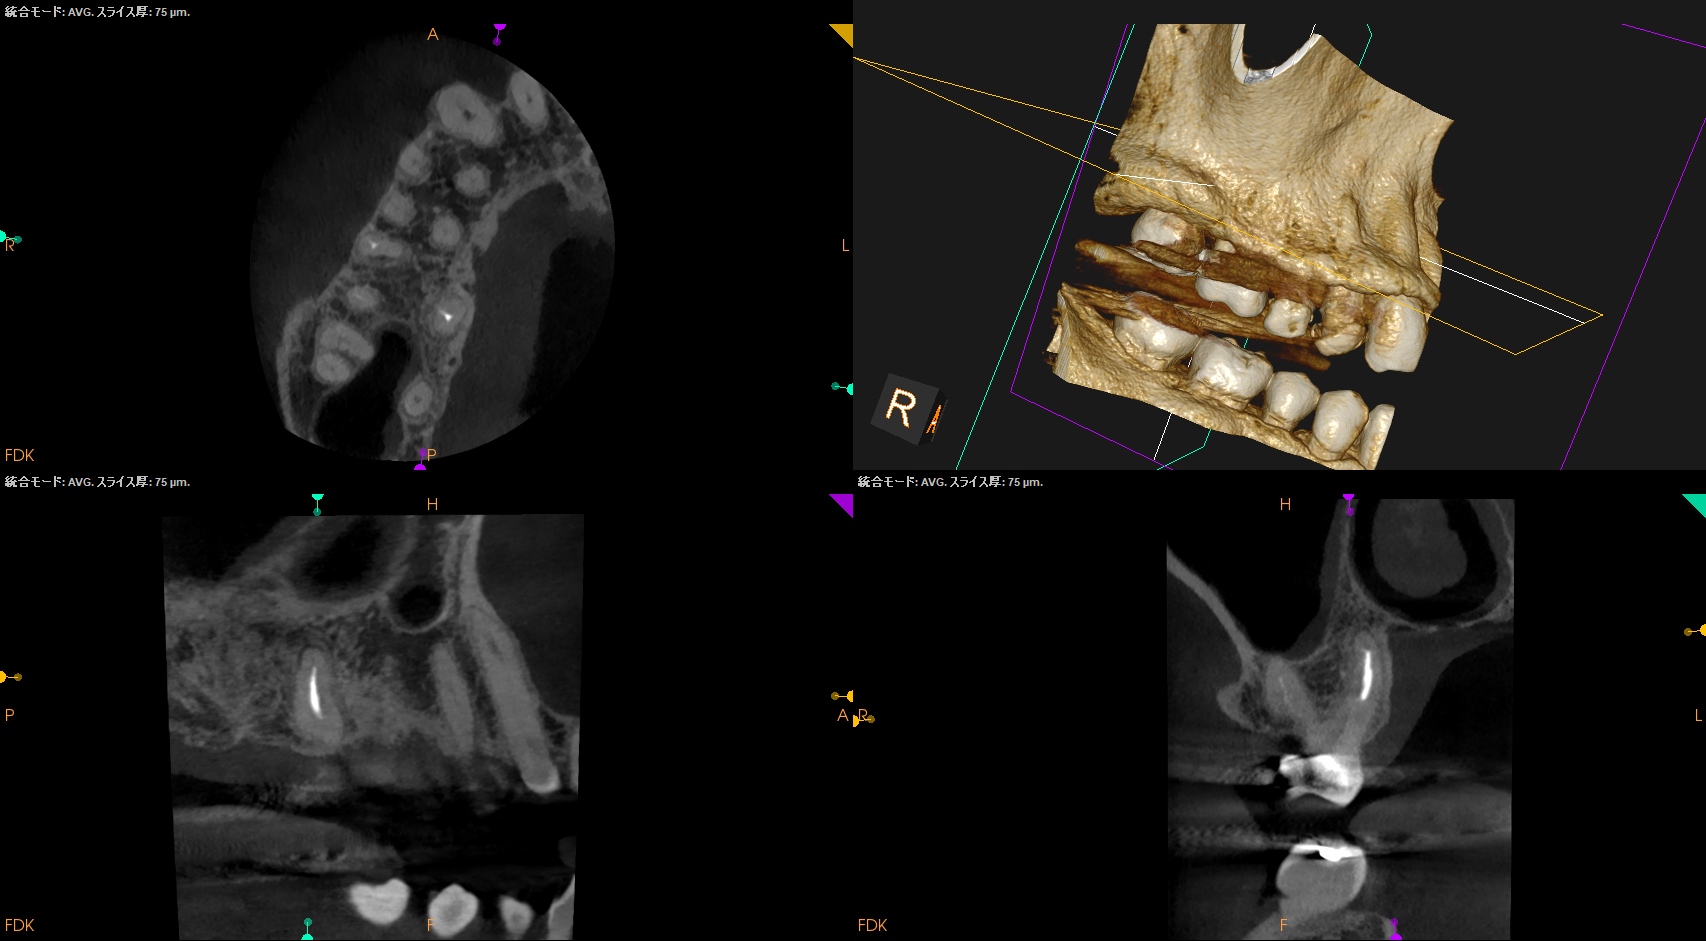

Pre-op